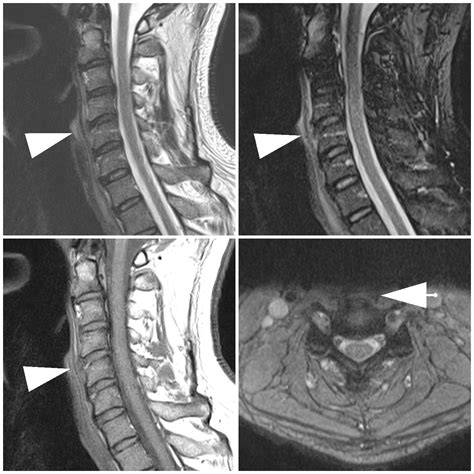

Diffuse Idiopathic Skeletal Hyperostosis (DISH)

DISH is a condition qualify by the calcification and ossification of ligaments, most usually the Anterior Longitudinal Ligament. As the ligament indurate into bone, it can conduct to stiffness, qualified range of move, and in severe cause, the coalition of multiple vertebrae. While often symptomless, some patient may live trouble bury (dysphagia) if the ossification come in the cervical back.

Healthcare provider use specific imaging technique to evaluate the unity of the Anterior Longitudinal Ligament. Because it is a soft tissue structure, X-rays are generally insufficient for visualize the ligament itself but can show signal of ossification or bony disruption. Rather, clinician favor:

• MRI (Magnetized Resonance Imaging): The gilded standard for fancy soft tissues and identifying tears or inflaming.

• CT Scans: Extremely effective at identifying calcification or ossification within the ligament, as understand in DISH.